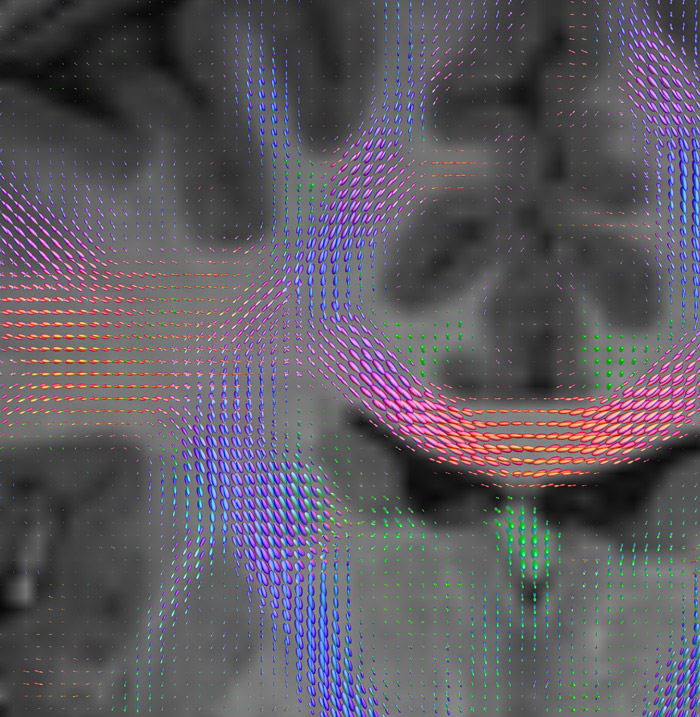

All images were created from the same acquisition in a child using Ingenia 3.0T CX and 32-channel dS Head coil. Diffusion data was acquired at b-values 0, 500, 1000, 2000, 3000. The use of high b-values (3000 s/mm2) effectively suppresses extra-axonal water signal and provides high angular resolution.

CSD of multishell DWI results in the white matter FOD at each voxel. Unlike the conventional diffusion tensor model, this approach enables accurate modeling of multiple fiber populations within a single voxel.

Crossings of the corpus callosum, corticospinal tracts, and the superior longitudinal fasciculus are shown.

Crossing fibers of the corpus callosum bordered by the superior longitudinal fasciculus as well as within in the pons.